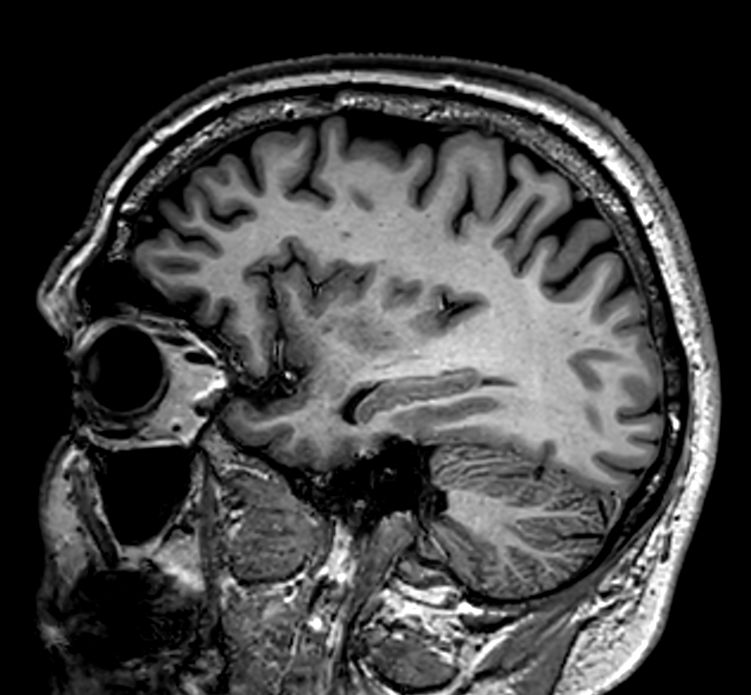

Sagittal 3D VIEW - T1w TSE